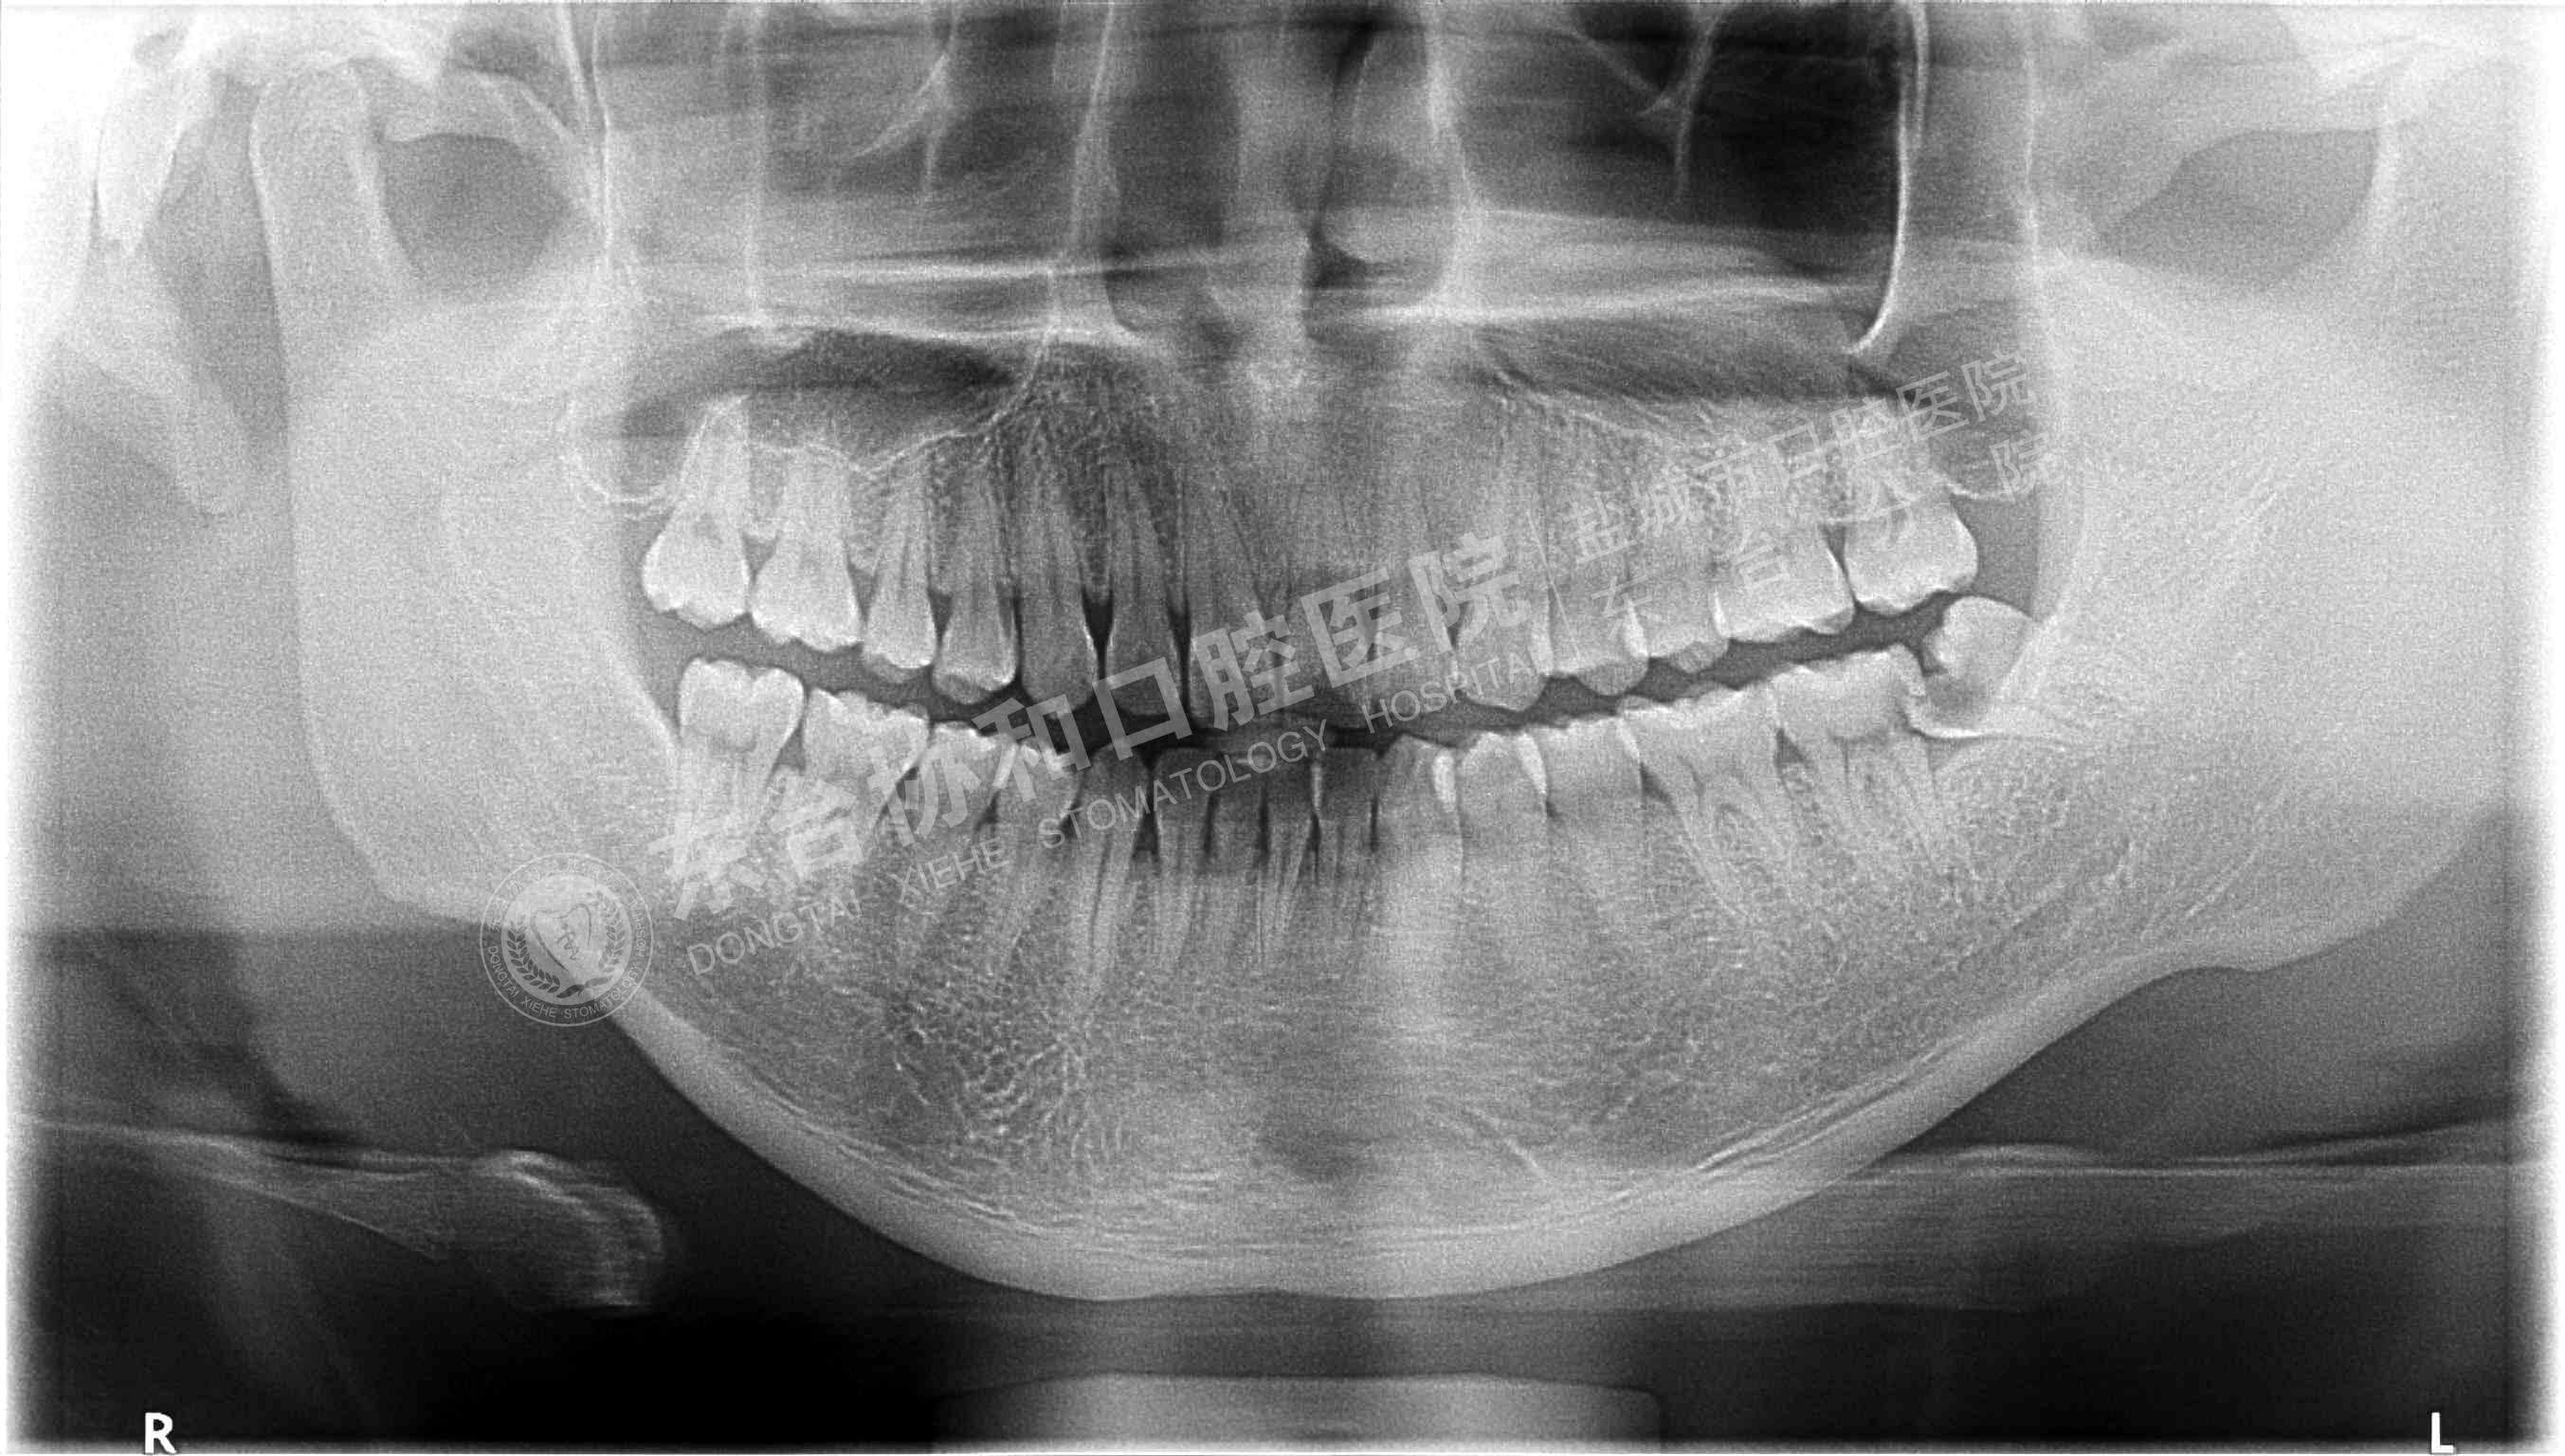

很多患者都很排斥拍牙片,認(rèn)為醫(yī)院是為了多收錢(qián)才讓他們拍的,其實(shí)這是一個(gè)錯(cuò)誤的想法,拍牙片是口腔科常用重要的檢查手段,臨床檢查只能直觀判斷牙冠和牙齦部分的情況,而對(duì)于牙根,牙槽骨、牙周膜等情況則必須通過(guò)牙片檢查。牙齒在牙片上顯示出白色阻射影像,其中牙釉質(zhì)阻射強(qiáng),牙本質(zhì)和牙骨質(zhì)阻射低于牙釉質(zhì),牙髓腔呈灰黑色影像,根管口至根尖孔呈逐漸變細(xì)的影像。

通過(guò)牙片除了了解牙齒的病變情況,還可以了解牙槽骨內(nèi)是否有埋伏牙、多生牙、牙源性腫瘤和囊腫等,依據(jù)牙片綜合分析可以提高牙齒診斷調(diào)節(jié)的準(zhǔn)確性和。

不同病種拍牙片的意義1、頜面部外傷:了解牙齒是否折裂、牙槽骨骨折程度和范圍。

2、牙齒硬組織病變:牙頸部牙根部齲齒、鄰面齲、確定齲壞的程度和齲壞的范圍;齲壞深度與牙髓腔的關(guān)系;了解齲壞與牙髓腔的距離;了解髓腔的變化情況和根尖周情況。

3、牙髓病變:牙片幫助檢查牙髓是否被吸收。

4、根尖周炎癥:了解病牙根管情況:如根管數(shù)目、粗細(xì)、彎曲度以及有無(wú)鈣化、有無(wú)內(nèi)吸收等情況;根管調(diào)節(jié)后的充填情況。如果牙齒需要做根管調(diào)節(jié),則牙片需要拍三張以上。調(diào)節(jié)前拍片是用來(lái)判斷是否根尖炎或者是囊腫的大小、范圍等,判斷是否需要根管調(diào)節(jié);根管預(yù)備術(shù)中片,檢查根管調(diào)節(jié)的長(zhǎng)度,調(diào)節(jié)后評(píng)價(jià)根管調(diào)節(jié)成功與否。

5、牙周炎癥:顯示牙槽骨吸收范圍和破壞程度。

6、用于阻生牙、埋伏牙及替換牙的檢查和調(diào)節(jié)。

7、牙片來(lái)確定乳牙和恒牙的相對(duì)位置,用來(lái)幫助醫(yī)生診斷乳牙是否能自行脫落還是需要拔除。

8、牙齒矯正:拍攝口腔全景片和頭顱側(cè)位片,以檢查骨骼和牙齒的發(fā)育情況。

9、拔牙檢查牙根情況以及牙槽骨破壞程度,牙齒是否拔除干凈以及牙槽窩形態(tài)是否完好。

10、種植牙拍牙片顯示牙槽骨的健康狀況、高度、密度,是否適合于種植牙;種植體的成活情況。